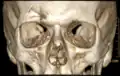

Impressionsbruch der Stirnhöhle in der Computertomographie: 3D-Rekonstruktion in Volume-Rendering-Technik. -